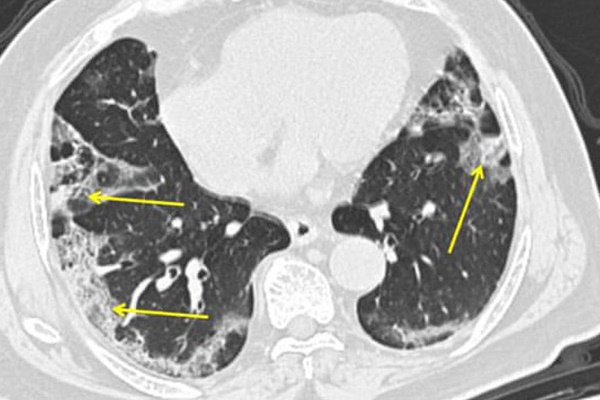

Bức ảnh cho thấy bản chụp CT của một bệnh nhân nhiễm COVID-19. Viêm phổi gây ra bởi virus corona khiến phổi có những vết mờ dễ thấy ở viền ngoài phổi. Ảnh: Mount Sinai Hospital/AP

Ông Wilson cho biết có bằng chứng cho thấy viêm phổi gây ra bởi COVID-19 có thể trở nên rất nghiêm trọng. Theo ông Wilson, các ca viêm phổi loại này thường bị ảnh hưởng tới toàn bộ phổi, thay vì một số phần nhỏ.